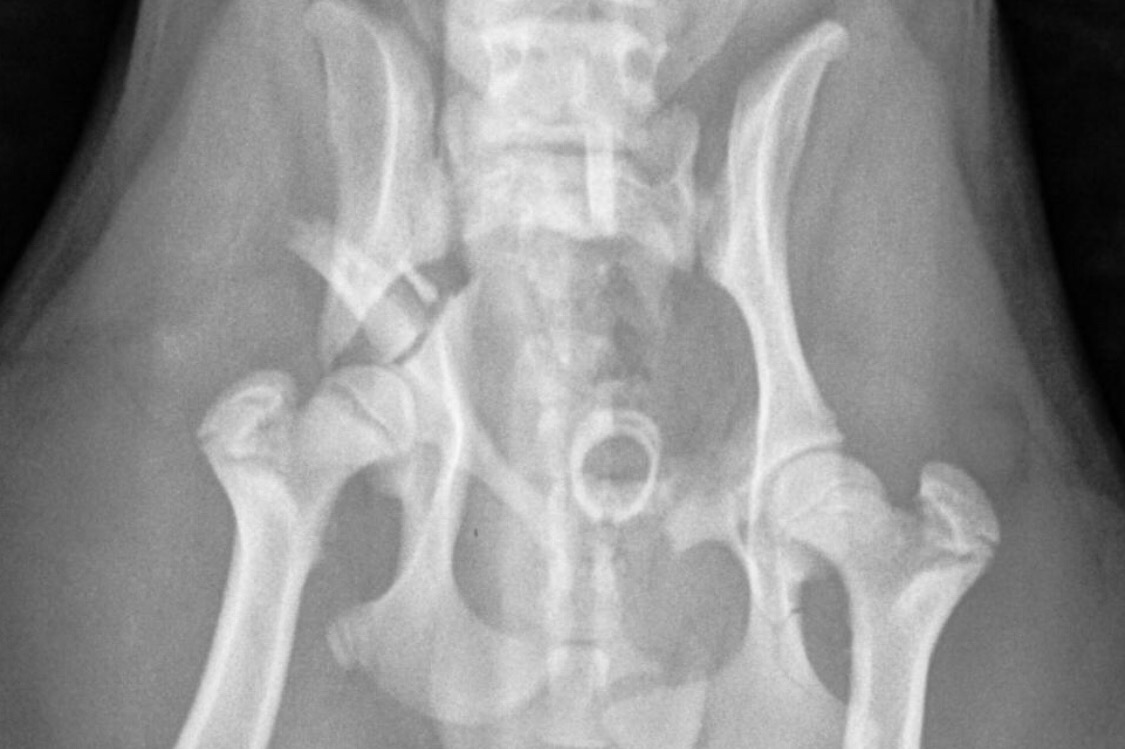

My 6 month old Shih Tzu puppy got hit by a car. He is in a critical condition and needs a surgery to fix multiple fractures in his pelvis. ASAP. Unfortunately my family has difficulty paying for the surgery. But me and my kids believe with all our hearts that all together we can save our little baby Pooshock and he can survive. I also applied for animal assistant league and trying to apply to other organizations. Thank you for your help, I hope together we can save a life.